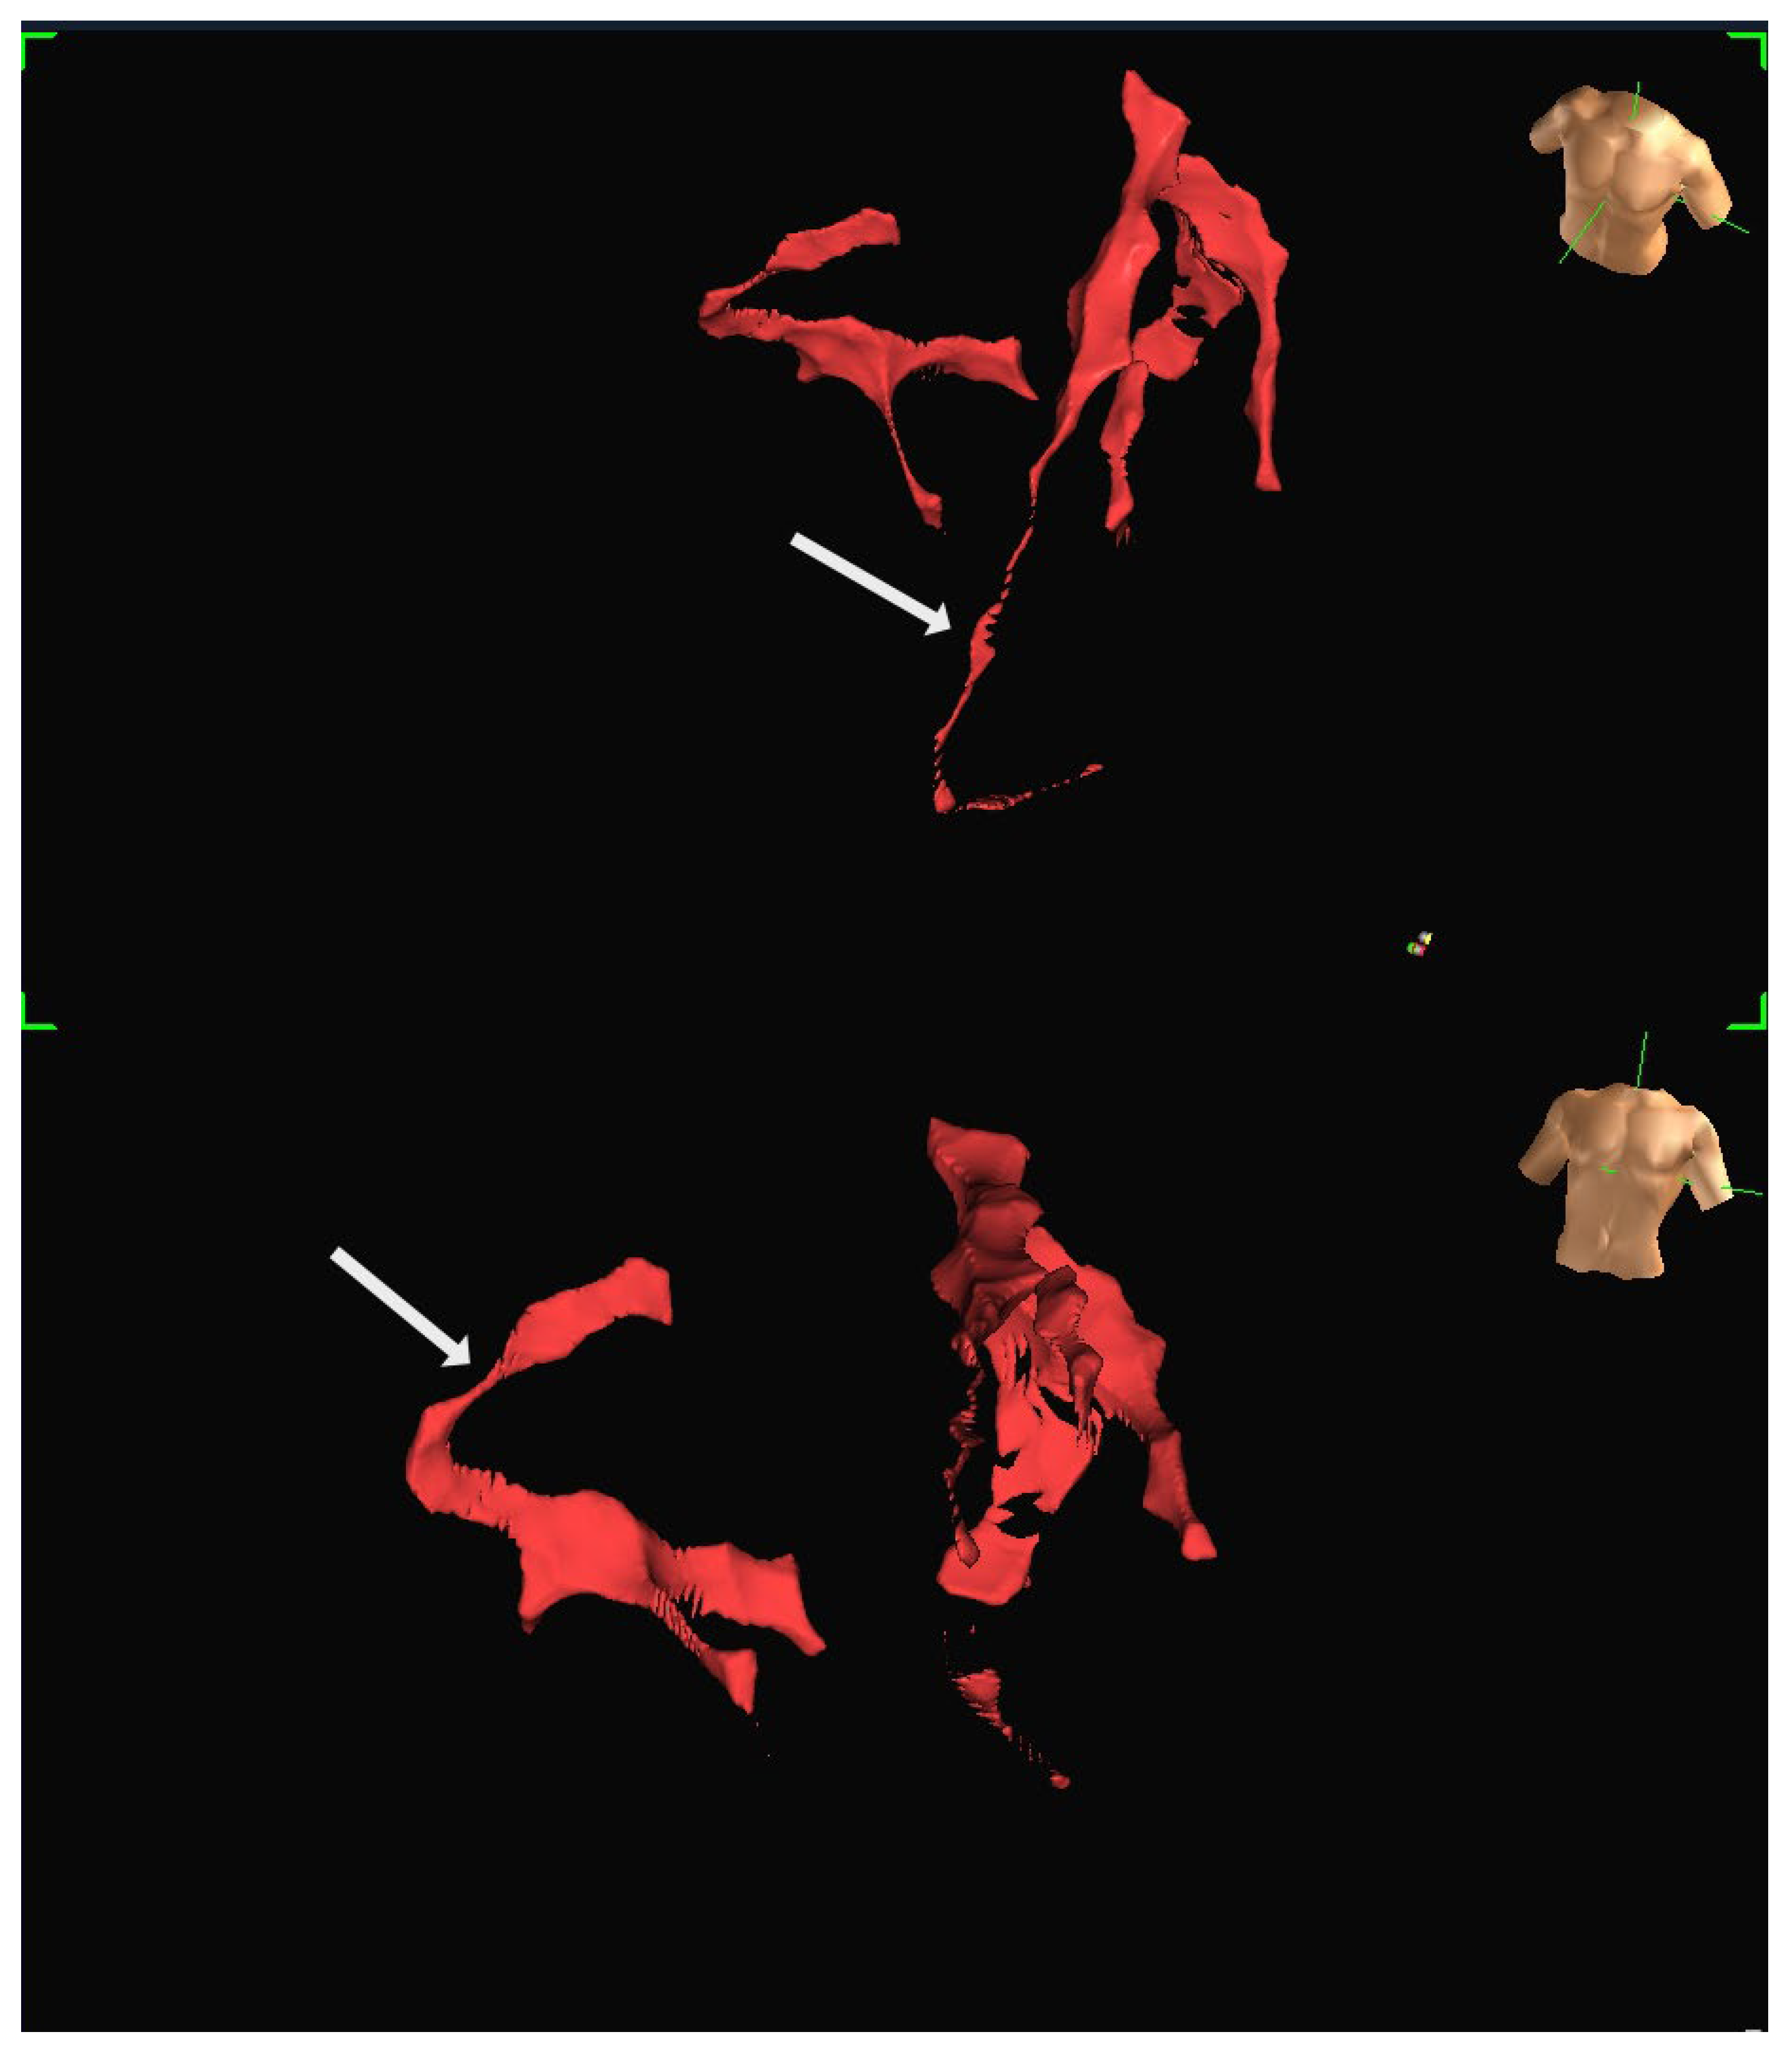

A human feasibility study involving multiple participants was conducted using the EnSite Precision system [13]. Insulated Sion Blue coronary guidewires (Asahi Intec, Japan) were tracked through epicardial arteries, including the left anterior descending and right coronary arteries, to produce anatomical reconstructions closely matching conventional angiographic images. The mapping system tracked the distal wire tip based on impedance field localisation. System accuracy was further evaluated in a custom-built water bath model incorporating segmented CT data. In this controlled setup, bipolar catheters fabricated from over-the-wire balloons and coronary wires were advanced through fixed vessel phantoms, confirming consistent localisation and map generation. Representative three-dimensional reconstructions generated using the EnSite Precision mapping system are shown in Figure 4 and Figure 5. These panels depict different views from the same patient, illustrating how coronary anatomy was mapped and visualised during the feasibility study.

Figure 4. Representative three-dimensional reconstruction of coronary anatomy generated using the EnSite Precision EAMS. The geometry was derived from guidewire tracking in a single patient. The coronary vessels are displayed in red: (Top) Left anterior oblique (LAO) projection, with the RCA marked by an arrow. (Bottom) Right anterior oblique projection (RAO), with LAD marked by an arrow. Torso icons indicate image orientation.

Figure 5. Additional views of the same patient dataset shown in Figure 4, demonstrating the ability to visualise the vessel course from different angles: (Top) The LAD is marked by an arrow. (Bottom) RCA is marked by an arrow. Both images are displayed in LAO projection at different angulations.